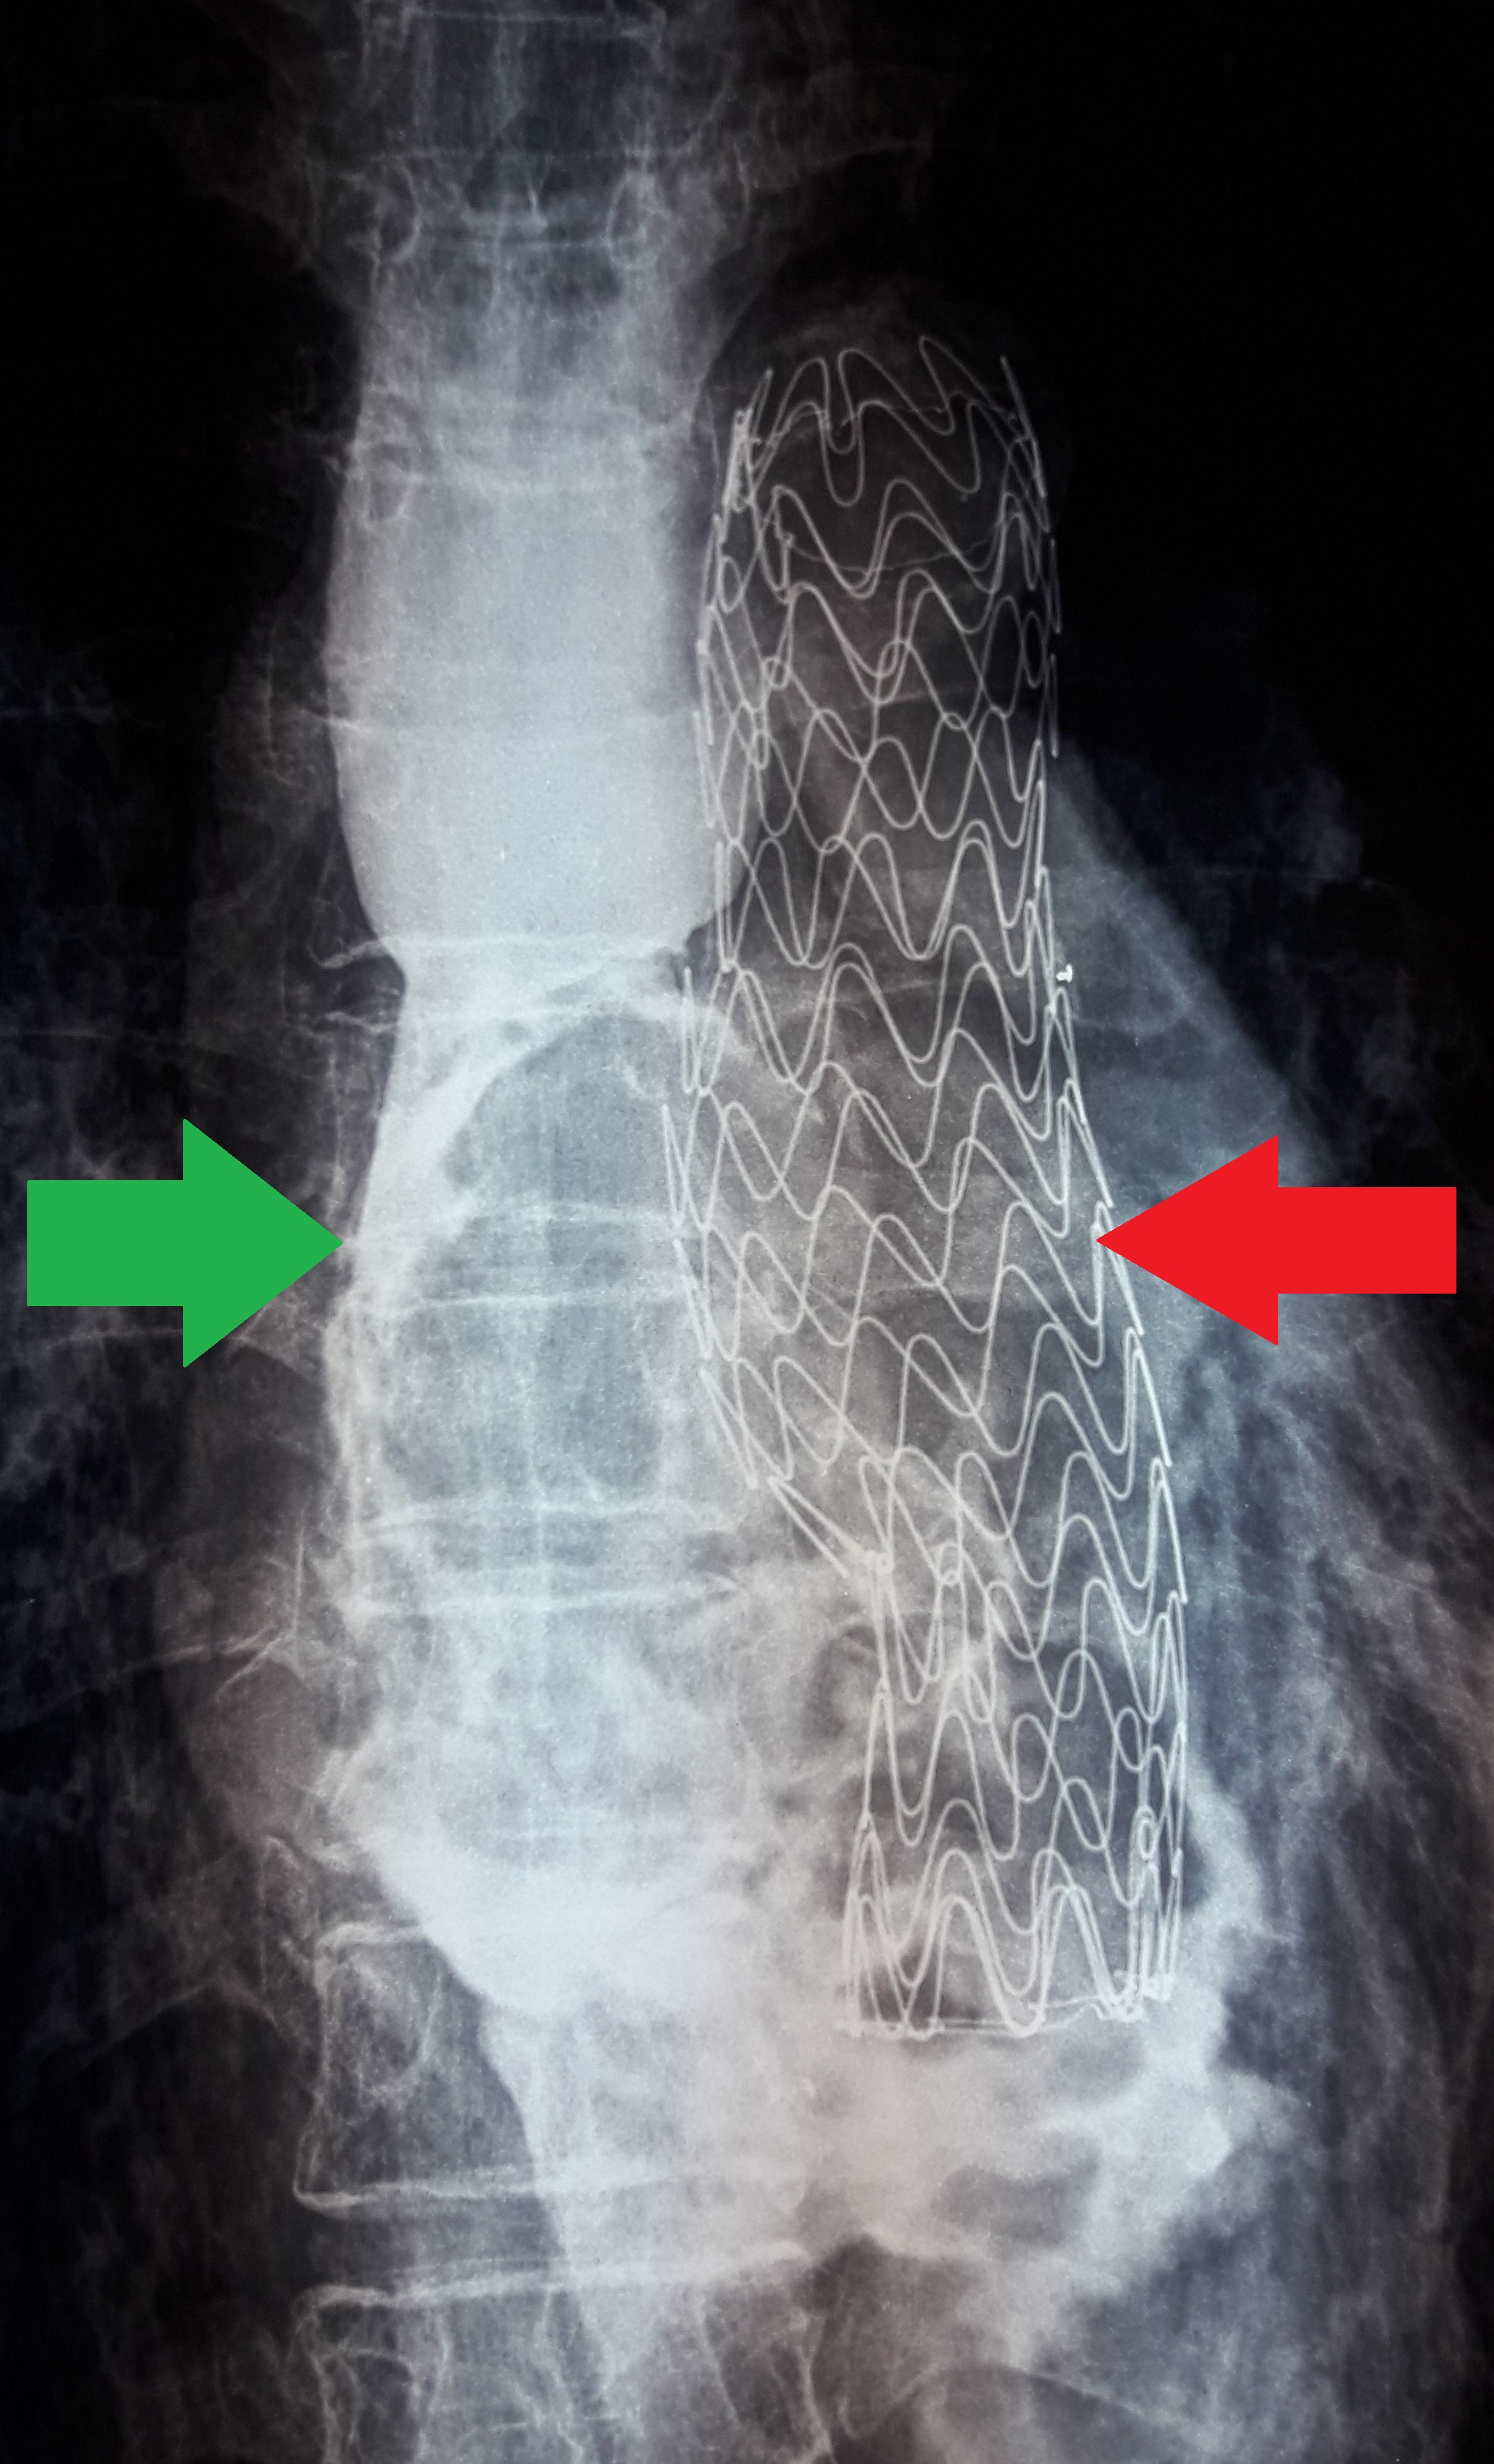

Οισοφαγικό (πράσινο βέλος) και θωρακικής αορτής (κόκκινο βέλος) stent σε θέση (Ευγενική παραχώρηση Dr. V. Penopoulos)

Οισοφαγογράφημα που ανέδειξε διαρροή σκιαγραφικού από μέσο οισοφάγο στο μεσοθωράκιο (πράσινο βέλος). Αορτικό stent σε θέση (κόκκινο βέλος) (Ευγενική παραχώρηση Dr. V. Penopoulos)